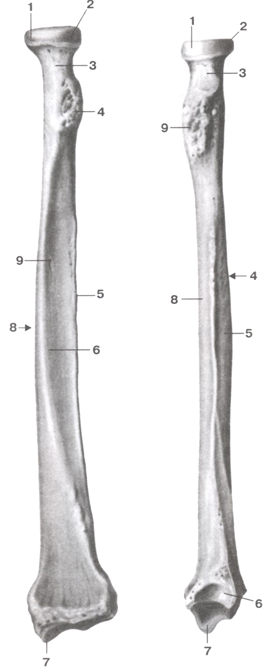

Радиоульнарный угол: строение и особенности лучевой кости